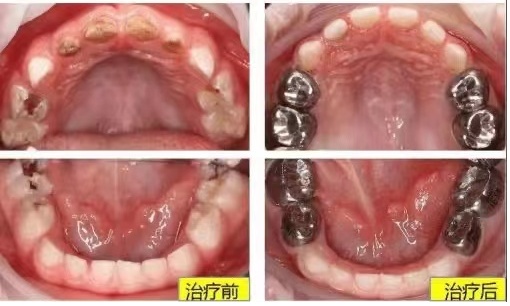

其实,如果小朋友乳牙缺损较大,难以充填或者严重磨耗以及根管治疗完成后,都建议做一个“小牙套”,既可以保护牙齿并增加牙齿的强度,又能够确保乳牙被恒牙顺利替换,这种“小牙套”就叫预成冠。后牙通常是不锈钢金属牙冠,就是我们常说的“小钢牙”,而前牙为了美观,通常为透明牙冠。

金属预成冠

前牙透明冠美观,能恢复解剖形态